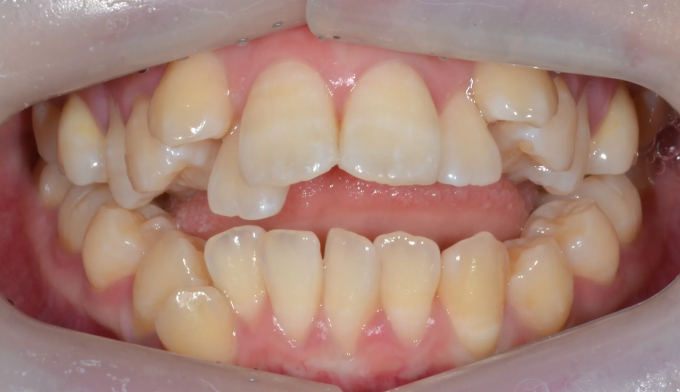

덧니,

돌출입

10대

2025.02.11